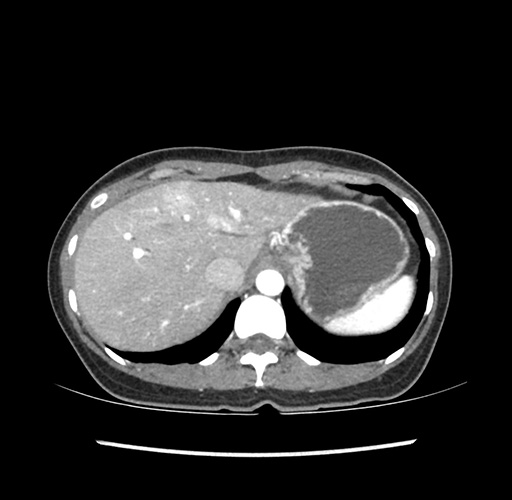

Imaging Analysis

Look through the patient's CT scan to identify any areas of concern for the necessary procedure.

Based on your CT findings, which issue(s) would give reason for "planned slowing down moment(s)" in this case?